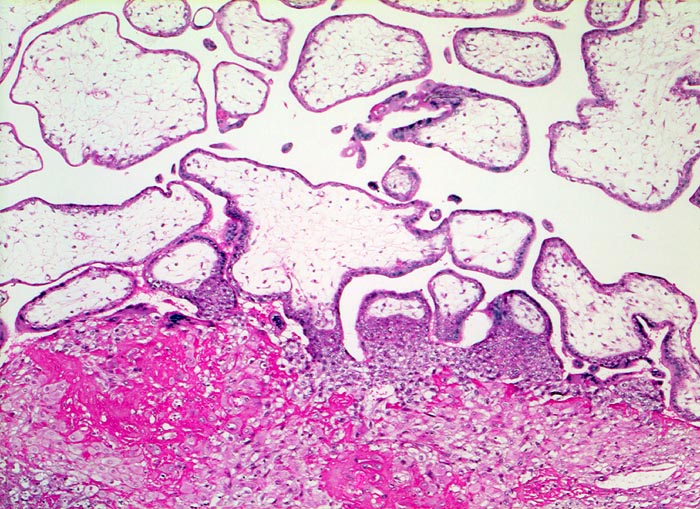

Morphologische Merkmale:

• Myometrium bedeckt von dezidualisiertem Endometriumstroma der Dezidua basalis.

• Invasion des Myometriums durch intermediären extravillösen Trophoblast.

• Fibrinoidschicht.

• Chorionzotten, ein Teil davon verankert mit dem dezidual transformierten Endometrium = Dezidua basalis (Haftzotten).

• Choriondeckplatte.

• Rechts oben Anteile des Chorion laeve.